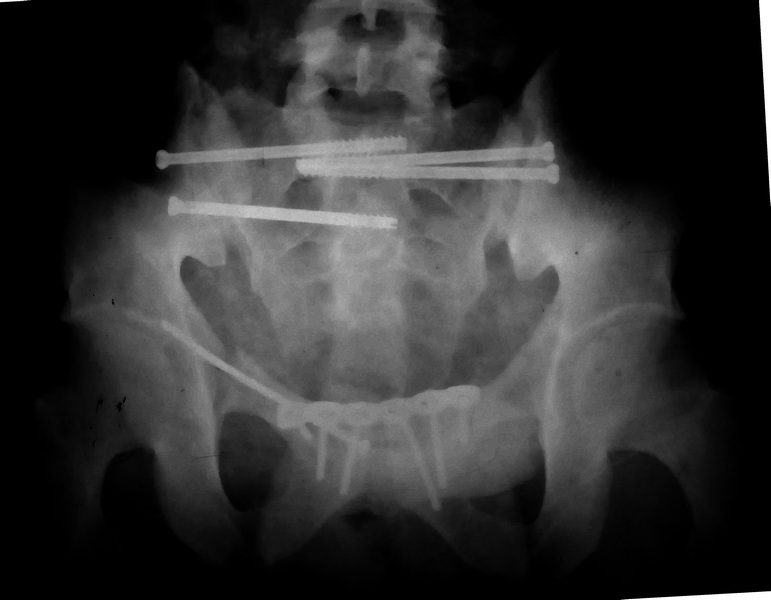

нагрузка после таза С3

Молодой парень, без соматики. Сейчас чуть больше 2-х нед после операции, швы сняты, мочится сам. Был тяжелый, после операции дней 10 пытался выполнить лежа поперечный шпагат (успешно, так и лежал большей частью, может быть из-за обширной гематомы промежности). Репозиция не идеальная, но фиксация довольно надежная, за 2 нед ничего не "разъехалось". Сейчас пришел в ум. Когда по-вашему можно дать нагрузку и на какую ногу или на обе? Или вообще подскажете программу реабилитации. PS Заранее извиняюсь за качество снимков, до не делали (body scan), если не видно - то - полные разрывы КПС с двух сторон. после КТ сломался. Неврологии вроде бы нет.